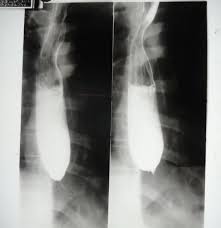

🩻 Difficulty 2 in swallowing – Suspected Esophageal Stricture

Difficulty 2 in swallowing – Suspected Esophageal Stricture

Case Images